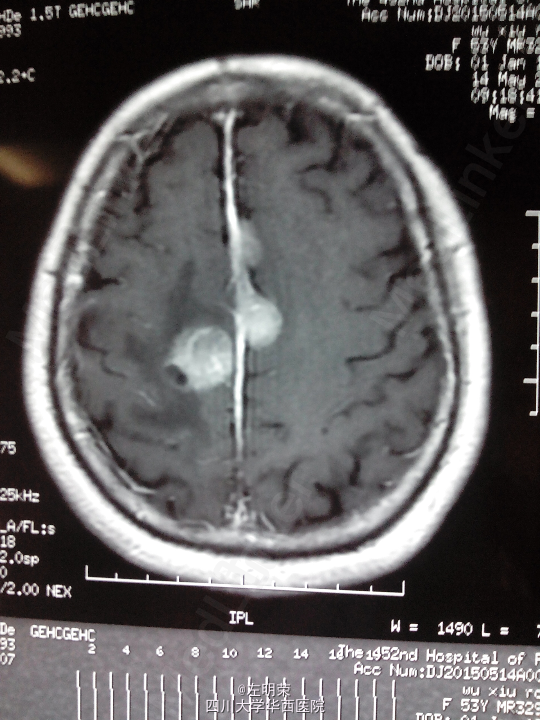

脑膜瘤术后复发(多发脑膜瘤)

左下肢乏力伴间断抽搐半年+, 患者于5年前行左侧额叶脑膜瘤切除术,术后行伽马刀治疗数次,近来出现肢体无力伴抽搐,不规律服用抗癫痫药物,昨日再发抽搐。

1、多发脑膜瘤 2、继发性癫痫

行占位切除术;待病理结果;术后应复查头部MRI,确定肿瘤切除情况,拟定下一步治疗方案。